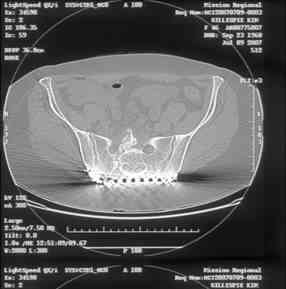

Re: Sacral Non-Union

Here is a magnified view. Sorry about the quality but the CT was scanned into our system.